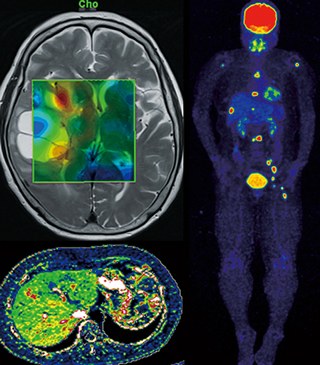

がん治療などにも活用される放射線診断学。未来の可能性を秘めた放射線診断学分野の研究室を訪ねました。

世界最先端の画像診断を通してよりよい医療人を育てる

放射線診断というと、診察のみを行うイメージがありますが、それだけではありません。同大学は「 IVR(アイ・ブイ・アール ※ )」という治療法で、世界トップレベルの症例数を誇ります。 IVRとは、画像を見ながらカテーテルと呼ばれる細い管や針を用いて詰まった血管を広げたり、かんを死滅させたりすることも可能な最先端医療です。

「PET-CT」や「3T MRI」、「64列マルチスライスCT」などの最先端の装置を多数導入して、高度な画像診断を行っている